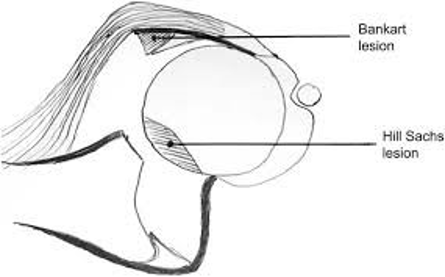

Durante una lussazione di spalla la testa omerale è forzata ad uscire e frequentemente va a danneggiare il cercine o labbro glenoideo cioè il bordo della superficie glenoidea che funge da struttura di contenimento della testa (questa viene chiamata lesione di Bankart). Insieme al cercine si possono lesionare anche i legamenti gleno-omerali e la capsula articolare. Se il trauma è di notevole entità la testa omerale può entrare in contatto violento con il margine osseo anteriore della glena e causando molto frequentemente una frattura della testa dell’omero (detta lesione di Hill Sachs). Anche il margine osseo anteriore della glena può lesionarsi e fratturarsi determinando una lesione denominata Bony Bankart.